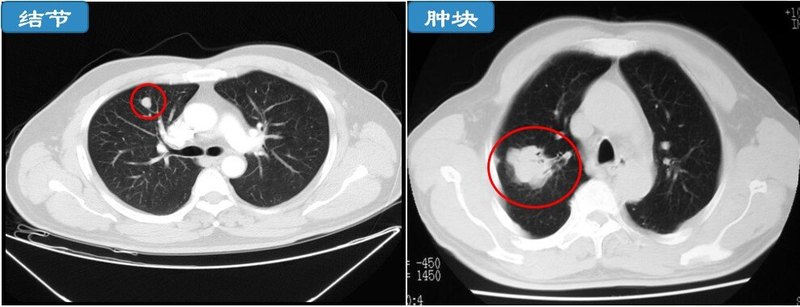

每年職工體檢一結(jié)束,門診就會(huì)增加許多前來(lái)咨詢肺部結(jié)節(jié)的患者,隨著CT分辨率的提高,查出的肺部結(jié)節(jié)也越來(lái)越多。肺部結(jié)節(jié)直徑較小,大部分是體檢發(fā)現(xiàn),無(wú)任何癥狀,所以很多患者對(duì)報(bào)告熟視無(wú)睹、不聞不問(wèn),而另一些患者則唯恐自己得了肺癌,整日擔(dān)驚受怕。其實(shí)這兩種態(tài)度都不可取,那我們?nèi)绾握_對(duì)待體檢發(fā)現(xiàn)的肺部結(jié)節(jié)?回答這個(gè)問(wèn)題之前我們需要了解幾個(gè)小知識(shí)。1.什么是肺結(jié)節(jié)?肺結(jié)節(jié)是指直徑小于或等于3cm的類圓形或不規(guī)則形的病灶(大于3cm稱之為腫塊,惡性可能更大),可以單發(fā)或多發(fā)。直徑小于5mm的結(jié)節(jié)稱為微小結(jié)節(jié),直徑越小惡性可能性越低。不同密度的肺結(jié)節(jié),它的惡變概率也不同,根據(jù)結(jié)節(jié)密度可分為實(shí)性結(jié)節(jié)、純磨玻璃結(jié)節(jié)和混合性磨玻璃結(jié)節(jié),其中混合性磨玻璃結(jié)節(jié)癌變的可能性最大,其次是磨玻璃結(jié)節(jié)和實(shí)性結(jié)節(jié)。研究發(fā)現(xiàn),90%以上肺結(jié)節(jié)是良性的。2.肺結(jié)節(jié)的成因有哪些?1)吸入有害顆粒引起的炎性結(jié)節(jié):人的肺是間接和空氣相通的,空氣中的細(xì)微顆粒都有可能進(jìn)入肺內(nèi)。隨著年齡越大,肺與空氣“交流”時(shí)間越長(zhǎng),期間不免會(huì)受到某些有害物質(zhì)(如香煙煙霧、粉塵、霧霾、油煙味、汽車尾氣等)的損害,引起炎性反應(yīng),產(chǎn)生結(jié)節(jié)。2)感染引起的炎性結(jié)節(jié):當(dāng)肺內(nèi)感染某些病原體時(shí)會(huì)產(chǎn)生炎性結(jié)節(jié),比如結(jié)核桿菌、真菌(隱球菌)、細(xì)菌等,這些結(jié)節(jié)通過(guò)抗感染治療后大部分都會(huì)吸收。3)良性腫瘤性結(jié)節(jié):如錯(cuò)構(gòu)瘤、硬化性血管瘤、不典型腺瘤樣增生(可發(fā)展為肺癌)等。4)早期肺癌性結(jié)節(jié):早期肺癌,如微浸潤(rùn)性癌(原位癌目前歸類到癌前病變),隨著時(shí)間推移,結(jié)節(jié)會(huì)逐漸增大,密度逐漸增濃(如下圖a-b-c每隔1年后隨時(shí)間增大增濃)。5)其他類結(jié)節(jié):如痰栓、畸形、肺動(dòng)靜脈瘺、肺內(nèi)淋巴結(jié)影等。知道了上述幾個(gè)知識(shí)點(diǎn),那我們?nèi)绾握_對(duì)待體檢發(fā)現(xiàn)的肺部結(jié)節(jié)?首先要做的是評(píng)估結(jié)節(jié)是否為肺癌的高危結(jié)節(jié)。如何評(píng)估?第一,你要明確你是否有肺癌的高危因素,高危因素主要有以下幾方面:(1)吸煙≥20包年(或400年支),或曾經(jīng)吸煙≥20包年(或400年支),戒煙時(shí)間<15年;(2)有環(huán)境或高危職業(yè)暴露史(如石棉、鈹、鈾、氡等接觸者);(3)合并慢阻肺、彌漫性肺纖維化或既往有肺結(jié)核病史者;(4)既往罹患惡性腫瘤或有肺癌家族史者。第二,你要找呼吸相關(guān)專科醫(yī)師評(píng)估肺結(jié)節(jié)外觀的“好與壞”。(1)結(jié)節(jié)外觀評(píng)估(建議薄層CT靶掃描):結(jié)節(jié)大?。航Y(jié)節(jié)大小與惡性程度成正比,定期觀察中結(jié)節(jié)逐漸增大提示惡性。結(jié)節(jié)形態(tài):惡性結(jié)節(jié)傾向于圓形、類圓形或不規(guī)則形態(tài)結(jié)節(jié)邊緣:惡性結(jié)節(jié)有分葉狀,伴毛刺、胸膜凹陷征等結(jié)節(jié)-肺界面:惡性結(jié)節(jié)界面不光整、毛糙(2)結(jié)節(jié)密度:混合性密度惡性程度高,如實(shí)性成分大于50%,剩余磨玻璃成分,該結(jié)節(jié)惡性可能大。在定期復(fù)查肺部CT觀察過(guò)程中如結(jié)節(jié)磨玻璃密度逐年增高,也常提示惡性。好了,讀到這里我們就應(yīng)該有開頭問(wèn)題的答案了。我們經(jīng)過(guò)上述評(píng)估后,如果你的結(jié)節(jié)是低危(肺癌低風(fēng)險(xiǎn))結(jié)節(jié),可以通過(guò)定期肺部CT觀察即可(根據(jù)結(jié)節(jié)大小,半年到1年復(fù)查);如果你的結(jié)節(jié)是高危(肺癌高風(fēng)險(xiǎn))結(jié)節(jié),則聯(lián)系胸外科醫(yī)師,根據(jù)情況采取外科干預(yù)辦法。友情提醒:肺部結(jié)節(jié)治療藥物較少,中醫(yī)藥治療結(jié)節(jié)部分有效,但建議去正規(guī)中醫(yī)或中西醫(yī)結(jié)合??浦委煛?

近來(lái)到我科咨詢肺小結(jié)節(jié)相關(guān)問(wèn)題的病友呈增多趨勢(shì),筆者在好大夫網(wǎng)站的留言咨詢上也有許多這方面的問(wèn)題,那我們?nèi)绾卫硇悦鎸?duì)這些肺小結(jié)節(jié)呢?肺部結(jié)節(jié)是指肺部出現(xiàn)的直徑小于3厘米的圓形病灶;其中病灶直徑大于等于1厘米的稱之為大結(jié)節(jié);小于1厘米的稱為小結(jié)節(jié)。隨著高分辨胸部CT等影像學(xué)技術(shù)的出現(xiàn),越來(lái)越多的小結(jié)節(jié)在臨床前被發(fā)現(xiàn),如何判斷它們是良性病變還是令人生懼的惡性腫瘤呢?醫(yī)生可以通過(guò)結(jié)合高分辨CT(HRCT),特別是螺旋CT來(lái)放大病灶的局部形態(tài)、觀察其周圍的情況,提高對(duì)肺部小結(jié)節(jié)的診斷能力。臨床上常常就小結(jié)節(jié)的影像學(xué)特點(diǎn)和其動(dòng)態(tài)變化情況、病員的自身癥狀等來(lái)綜合地判斷病灶的性質(zhì)。在國(guó)際上Fleischner學(xué)會(huì)提出的肺小結(jié)節(jié)處理指南,綜合了多個(gè)詢證醫(yī)學(xué)證據(jù),目前廣泛應(yīng)用,現(xiàn)簡(jiǎn)單介紹如下:該指南將觀察人群分為低風(fēng)險(xiǎn)和高風(fēng)險(xiǎn)患者,高風(fēng)險(xiǎn)患者包括吸煙和已知的風(fēng)險(xiǎn)因素(包括慢性肺部疾病,肺部腫瘤病史等)。針對(duì)低風(fēng)險(xiǎn)人群:結(jié)節(jié)小于等于4mm:無(wú)須隨診;4-6mm :12月隨診,如果無(wú)變化,停止;6-8mm:6-12月隨診一次,如果無(wú)變化18-24月隨診一次;大于8mm: 3、9、24月進(jìn)行增強(qiáng)CT、PET或穿刺檢查。針對(duì)高風(fēng)險(xiǎn)人群: 結(jié)節(jié)小于等于4mm:12月隨診,如果無(wú)變化,停止;4-6mm :6-12月隨診一次,如果無(wú)變化18-24月隨診一次;6-8mm:3-6月隨診一次,如果無(wú)變化,18-24月隨診一次;大于8mm: 同低危險(xiǎn)人群同時(shí)需注意:1.已知惡性腫瘤患者隨診時(shí)間應(yīng)縮短;2.35歲以下人群肺癌發(fā)生率極低,小于1%,且對(duì)放射線敏感,隨診需慎重,應(yīng)低劑量掃描;3.發(fā)熱患者應(yīng)考慮到炎癥可能,抗感染后復(fù)查或短期復(fù)查推薦;4.位于上葉的病變肺癌較多見;5.篩查檢出吸煙患者癌的致命性顯著高于非吸煙者,且病灶生長(zhǎng)速度顯著高于非吸煙者6.小于4mm的結(jié)節(jié)基本為良性,即使對(duì)于吸煙患者,其惡性率小于1%;7.大于8mm的篩查病灶惡性的可能性為10-20%,應(yīng)該采取更為積極的治療手段。